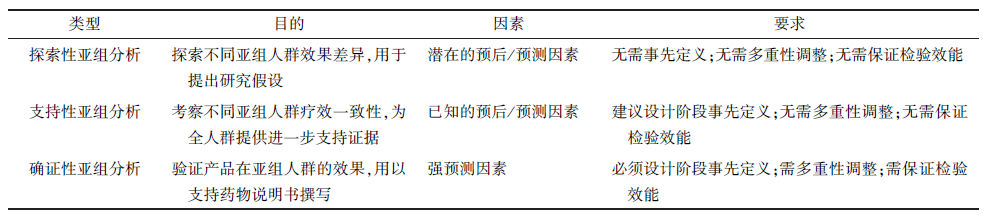

еӣҪ家иҚҜе“Ғзӣ‘и§ҶжІ»зҗҶеұҖиҚҜе“Ғе®ЎиҜ„дёӯеҝғпјҲcenter for drug evaluation, CDEпјүе°Ҷдәҡз»„еү–жһҗеҲҶдёә3 з§Қзұ»еһӢ����пјҢеҢ…жӢ¬:зЎ®иҜҒжҖ§дәҡз»„еү–жһҗгҖҒж”ҜжҢҒжҖ§дәҡз»„еү–жһҗе’ҢжҺўзҙўжҖ§дәҡз»„еү–жһҗпјҲеӣҫ1пјү[7]����пјҢдәӢе…Ҳз•ҢиҜҙгҖҒеӨҡйҮҚжҖ§и°ғи§ЈгҖҒзЈЁз»ғж•ҲиғҪжҳҜеҢәеҲ«дәҡз»„еү–жһҗзұ»еһӢзҡ„3дёӘиҰҒе®із»ҹи®ЎеӯҰзү№еҫҒ[8-9]��гҖӮдёәзҹҘи¶ізЎ®иҜҒжҖ§иҰҒжұӮ����пјҢйңҖеңЁз ”究дёӯйў„и®ҫдәҡз»„еҲҶеұӮйҡҸжңә并еҗҢж—¶й’ҲеҜ№ж„Ҹеҗ‘жҖ§жІ»з–—пјҲintent to treat����пјҢITTпјүеҺҹеҲҷе’Ңзү№е®ҡдәҡз»„зӣҳз®—ж ·жң¬йҮҸ����пјҢд»ҘеҢ…з®ЎиҜҘдәҡз»„е…·жңүи¶іеӨҹзҡ„з»ҹи®ЎеӯҰзЈЁз»ғж•ҲиғҪ����пјҢдё”йңҖжҺҘзәіеҗҲйҖӮзҡ„жҲҳз•ҘжҺ§еҲ¶жҖ»дёҖзұ»иҝҮеӨұα����пјӣеҺҘе…№й’ӣиҠҜеҸҜжқ“����пјҢFLAURAжҺҘзәіеәҸиҙҜеӨҡйҮҚзЈЁз»ғ����пјҢз»ҹи®Ўеү–жһҗйЎәеәҸдёәPFS-жҖ»з”ҹж¶ҜжңҹпјҲOverall Survival����пјҢOSпјү-дәҡз»„PFS����пјҢеҫҲеҘҪең°жҺ§еҲ¶дәҶжҖ»дҪ“Iзұ»иҝҮеӨұ����пјҢдҪҶе…¶и„‘иҪ¬з§»дәҡз»„PFSзҡ„ж•ҲжһңжҳҜеңЁOSеү–жһҗж•Ҳжһңд№ӢеүҚе®Јеёғзҡ„[1]��пјӣAENEASгҖҒFURLONG еҲҷеҲ’еҲҶдёҫиЎҢзЈЁз»ғ��гҖӮдҪҶдёүйЎ№з ”з©¶еқҮжңӘй’ҲеҜ№и„‘иҪ¬з§»дәҡз»„зӣҳз®—ж ·жң¬йҮҸ����пјҢзјәд№Ҹи¶іеӨҹзҡ„зЈЁз»ғж•ҲиғҪеҜ№и„‘иҪ¬з§»дәҡз»„еҒҡеҮәзЎ®иҜҒжҖ§з»“и®ә����пјҢеӣ жӯӨд»…иғҪдҪңдёәж”ҜжҢҒжҖ§дәҡз»„еү–жһҗ��гҖӮ

еӣҫ1. дәҡз»„еү–жһҗзұ»еһӢеҸҠиҫғйҮҸ